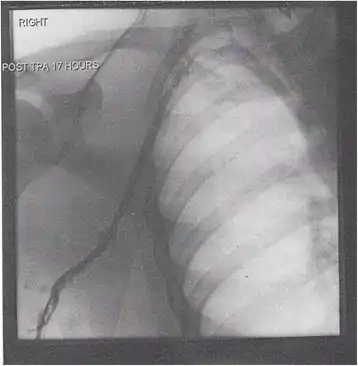

A venogram before catheter-directed thrombolysis for Paget–Schroetter syndrome, a rare and severe arm DVT shown here in a judo practitioner, with highly restricted blood flow shown in the vein

After treatment with catheter-directed thrombolysis, blood flow in the axillary and subclavian vein were significantly improved. Afterwards, a first rib resection allowed decompression. This reduces the risk of recurrent DVT and other sequelae from thoracic outlet compression.[147]

In DVT in the arm, the first (topmost) rib can be surgically removed as part of the typical treatment when the DVT is due to thoracic outlet syndrome or Paget–Schroetter syndrome. This treatment involves initial anticoagulation followed by thrombolysis of the subclavian vein and staged first rib resection to relieve the thoracic outlet compression and prevent recurrent DVT.[146]